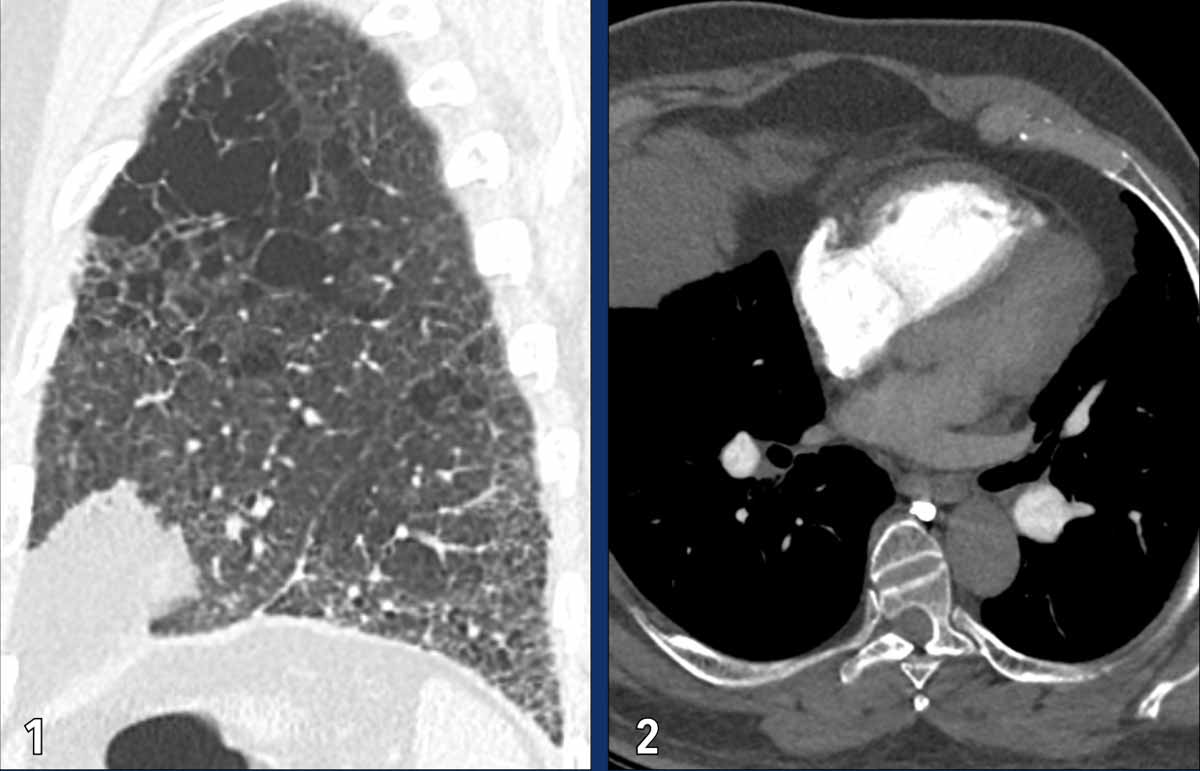

These images are of a young female with idiopathic PAH.

Imaging findings

1. Mild dilatation of the main pulmonary artery

2. Mild dilatation of the right ventricle.

3. Mild wall thickening of the right ventricle outflow tract (arrow).

The left atrium has a normal size.

4. Normal lung parenchyma.

PVOD

Pulmonary veno-occlusive disease (PVOD) is a rare subtype of PAH.

It is caused by narrowing and obliteration of the small pulmonary veins (venules), as opposed to other causes of group 1 pulmonary hypertension in which the pre-capillary arteries are primarily involved.

The venous occlusion leads to post-capillary pressure build-up and subsequently pulmonary arterial hypertension.

The classic CT triad in PVOD includes:

1. Smooth interlobular septal thickening.

2. Centrilobular ground-glass opacities.

3. Enlarged mediastinal and hilar lymph nodes resulting from chronic lymphatic congestion.